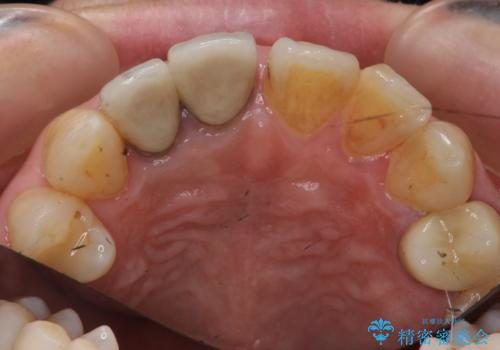

右上2本を以前セラミックにしたが、前歯のすき間が広がってきてしまったとのこと。

右上の前歯のみの被せなおしですと、右上の前歯が反対側に比べて極端に大きくなってしまうことを説明し、左上の前歯も併せてセラミックにすることにしました。

右上の前歯二本、左上の前歯1本をセラミックにし、正中の前歯を2本連結しました。

- 60.5万円(税込み) ジルコニアクラウンスペシャル 14.3万円x3 仮歯 1.1万円x3 右上1、右上2:ファイバーコア 2.2万円x2 右上1: 精密根管治療(リトリートメント) 9.9 万円x1費用は治療当時の料金となります